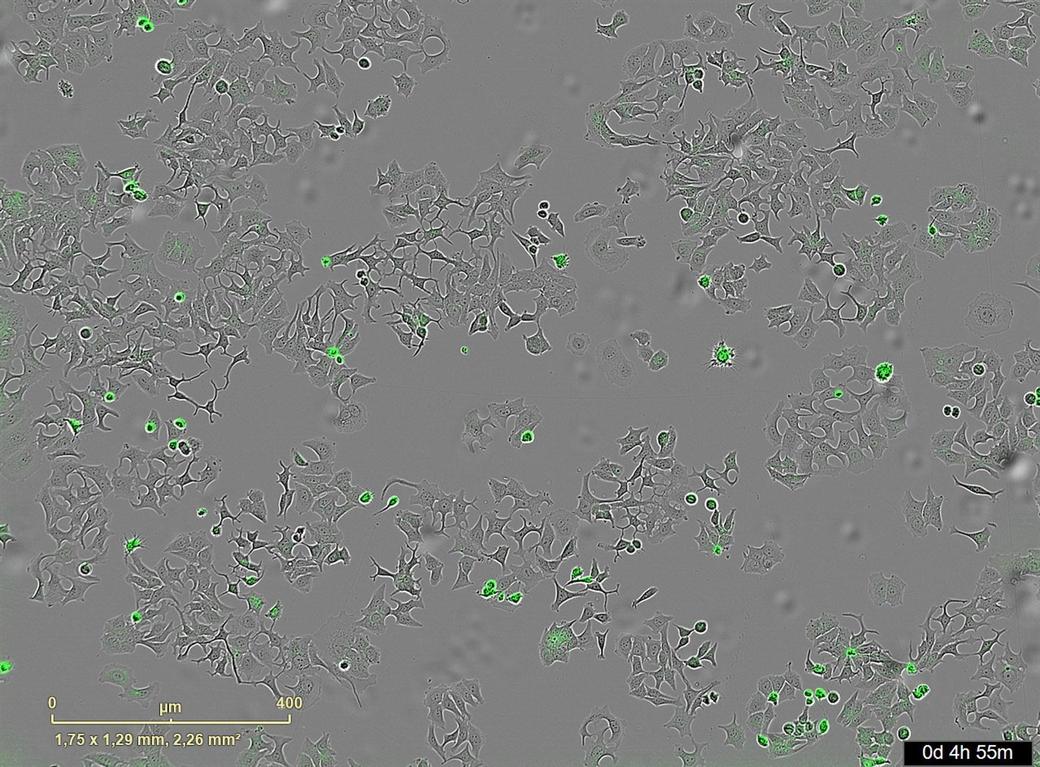

Cercetătorii au testat acest nou mecanism pe celule tumorale umane de sân, colon şi pancreas. Analiza a arătat că această proteină, numită HapA, este secretată de bacteria Vibrio cholerae, cunoscută în principal ca agent patogen al holerei.

Cercetările au fost efectuate pe linii celulare de cancer de sân, colorectal şi pancreatic, unde aplicarea substanţelor secretate de bacterii, în special HapA, a condus la distrugerea selectivă a celulelor maligne.